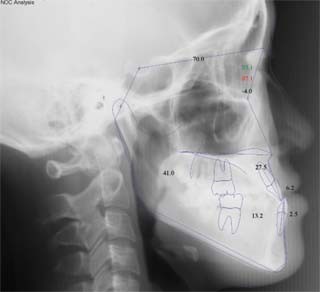

主訴:顎の歪み

診断名:骨格性下顎左方偏位

年齢:24歳

使用した主な装置名:TPB、マルチブラケット装置

抜歯/非抜歯および抜歯部位:非抜歯

治療期間:動的処置1年6か月、経過観察3年

費用の目安:保険適応 自己負担金として30~50万

リスク、副作用:外科手術によるリスク、マルチブラケット治療に伴う歯根吸収など偶発症が発生するリスクがある。

極めて強い側方変位を認めます。前後的・垂直的な問題は見られません。大きなズレであれば、外科的に骨のズレを改善する治療が選択されます。横断的な問題はその他の不正咬合と比較して、解決がかなり難しい事が多いです。治療後の後戻りが頻繁に見られる不正咬合ですので、外科矯正での改善が望ましい場合も多いでしょう。

このケースでは、外科手術は、上顎の傾斜の改善をLeFort1にて、下顎の正中の改善をSSROにて行いました。